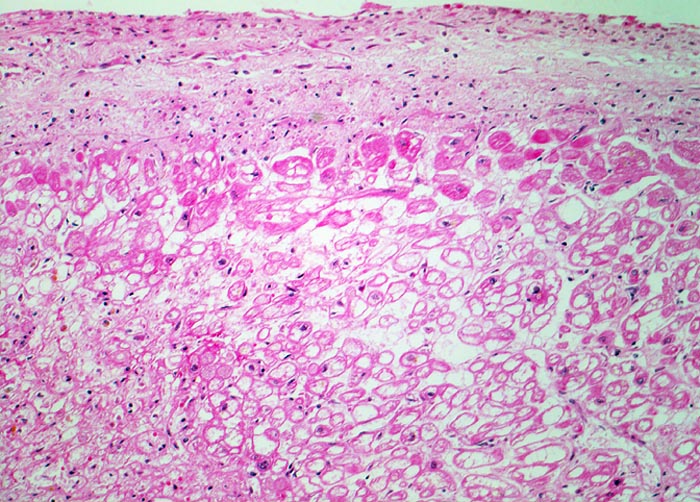

Luminaler Anteil der linken Herzkammer: Das unmittelbar subendokardial lokalisierte Myokard wird aus dem Herzblut per diffusionem mit zusätzlichem Sauerstoff versorgt. Bei einem Verschluss der Koronargefässe ist dieses Myokardareal von der Nekrose ausgespart und zeigt lediglich Zeichen der ischämischen Schädigung. Ischämisch geschädigte Muskelfasern mit erhaltenen Kernen und blasigem vakuolisiertem Sarkoplasma (= tubuläre Degeneration = Holundermarkzellen = massive Glykogenspeicherung).

Die hypoxisch bedingte vakuoläre (=tubuläre) Degeneration beruht auf einem Verlust der Myofibrillen und Glykogenspeicherung. Die zentral leeren Myokardzellen werden auch Holundermarkzellen genannt. Die veränderten Kardiomyozyten sind noch vital aber können sich nicht mehr kontrahieren. Das Auftreten der vakuolären Degeneration ist korreliert mit Herzinsuffizienz.